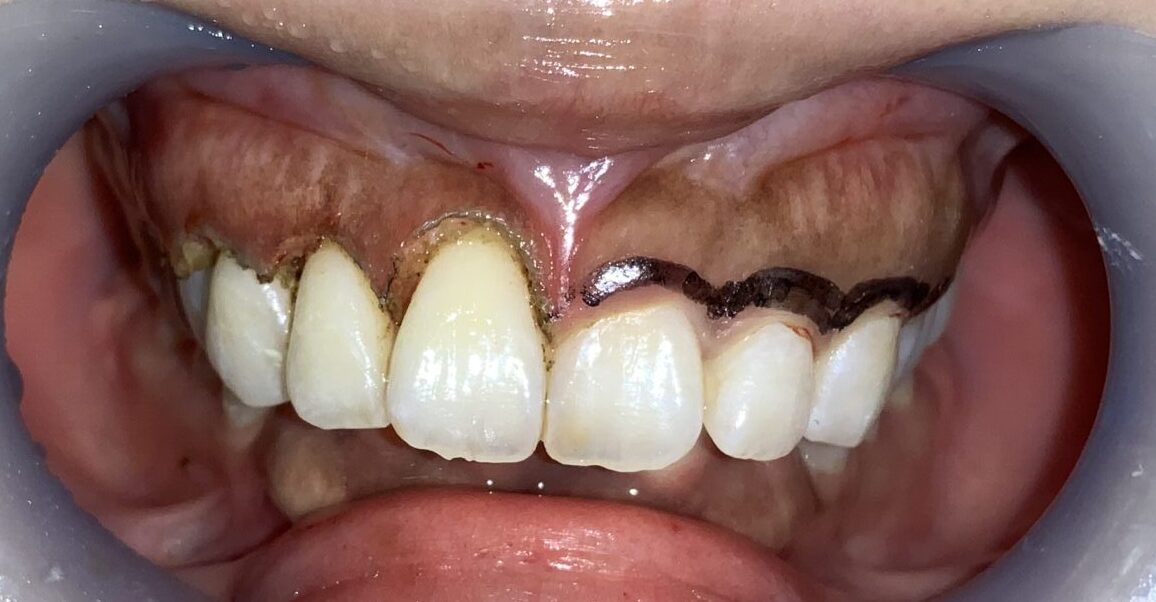

反対側の歯も全て整えました。

治療は歯冠長延長術専用の電気メスで処置します。手術時間は10分程度です。

費用は見えるところ、前歯の6本から10本の範囲で11万円です。本数は患者様のご希望に合わせて治療をしており、追加費用はありません。(多くの患者様から、安すぎて怪しいとお叱りを受けます。)

この治療方法の最大の魅力は歯冠長延長術にはデメリットがありません

歯ぐきの面積、形、色を整えることができて、デメリットがない点が大きな利点です。

さらに、歯冠長延長術をおこなった後は、後戻りはありません